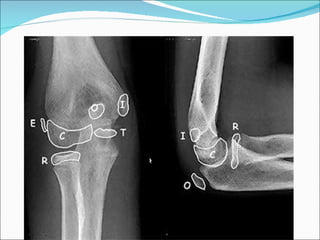

Ossification Centres

Mnemonic CRITOE

๏‚— C - capitellum

๏‚— R - radial head

๏‚— I - Internal Epicondyle

๏‚— T - Trochlea

๏‚— O - Olecranon

๏‚— E - External Epicondyle

Age at appearance   Age at Closure

Capitellum   1-2                 14

Radius       3                   16

Internal     5                   15

Epicondyle

Trochlea     7                   14

Olecranon    9                   14

External     11                  16

RADIOGRAPHYnot ossified then

โ€ขRadiographs if the lateral condyle and capitellum have

โ€ขradiographic findings can be subtle

โ€ขcontra-lateral radiographs are very important

โ€ขinternal oblique view most accurately shows maximum displacement and

fracture pattern,

- with the arm internally rotated will best demonstrate amount of

displacement & rotation of lateral condyle fragment;

- often multiple oblique radiographs will be needed to accurately

determine whether frx is displaced or non displaced;

Lateral Condyle fractures x rays .

The diagnosis of a lateral condyle fracture can be challenging.

Fracture lines are sometimes barely visible .

Remembering the fact that the lateral condyle fracture is the second most common

elbow-fracture in children and because you know where to look for will help you

lateral condyle fracture. On the x-ray only a small metaphyseal fragment is

visible. The detatched fragment however is larger than it appears on the

radiograph. The fracture extents into the lateral ridge of the trochlea. Elbow is

probably unstable.